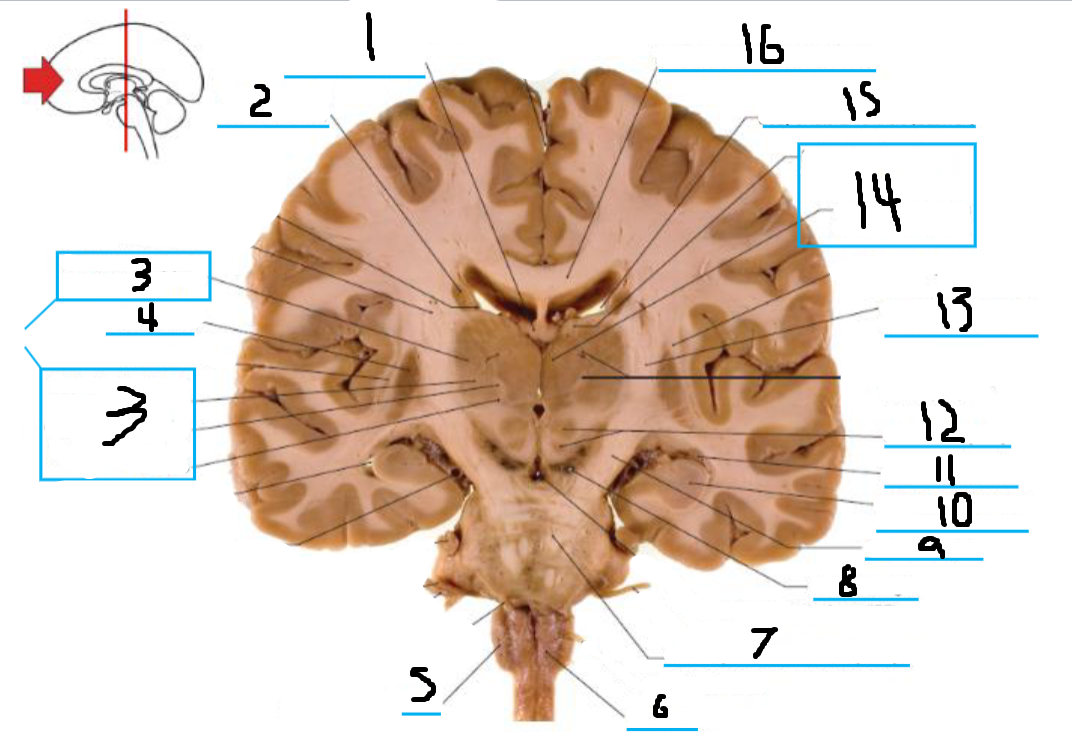

#1 is the:

Corpus Callosum

#2 is the:

Lateral Ventricle

#3 is the:

Septum Pellucidum

#4 is the:

#5 is the:

Insula

#6 is the:

Cingulate Gyrus

#7 is the:

Caudate

#8 is the:

Internal Capsule

#9 is the:

Putamen